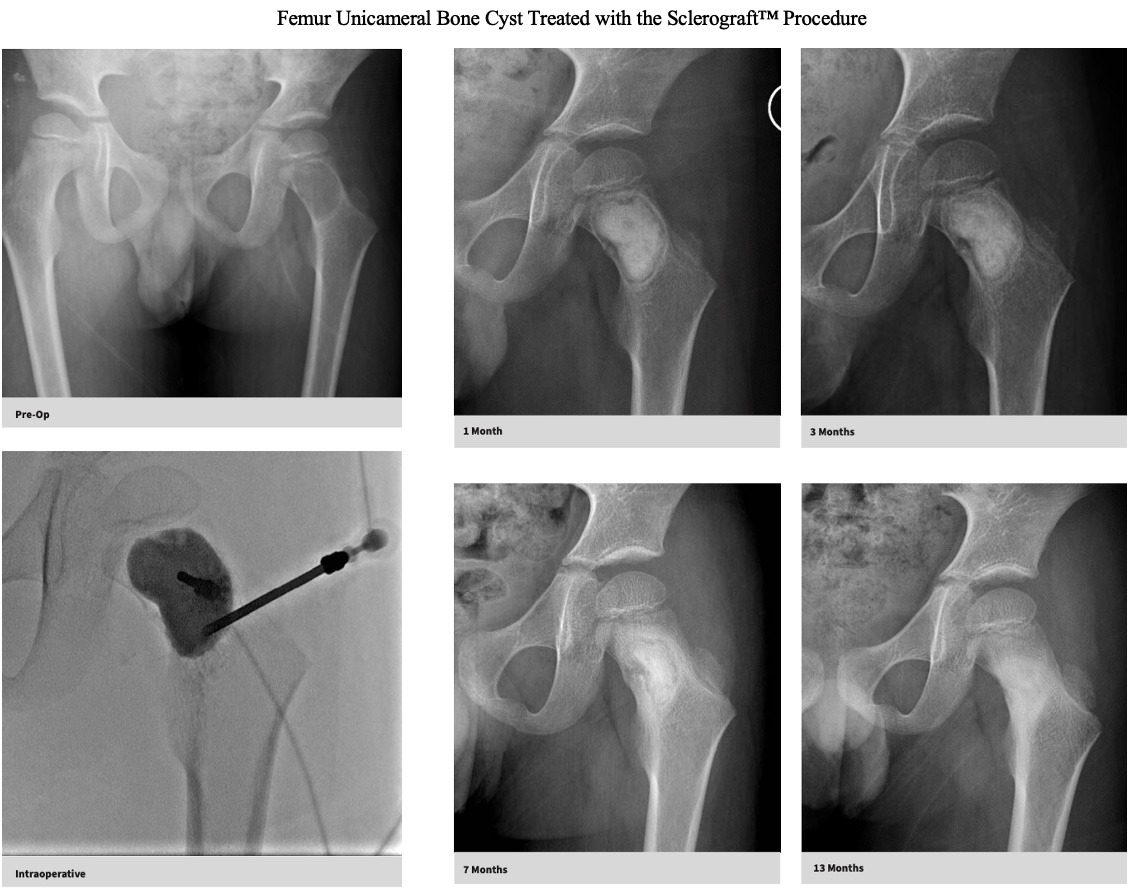

The Sclerograft procedure is a minimally invasive outpatient procedure used to treat bone cysts.

Utilizing needles, chemical sclerosis destroys the cyst wall and regenerative bone graft is injected via the needles to expedite bone healing.

The doctor uses imaging guidance (like X-ray or ultrasound) to guide needles into the cyst.

Chemical sclerosis using chemicals like doxycycline are washed through the cyst to kill the cyst wall lining

Regenerative bone graft is then injected through the needles and the needles are removed. The bone graft is temporary and is eventually reabsorbed by the body.

Quick recovery and bone formation seen between 6 weeks to 3 months

Gallery

Explore our educational resources and images